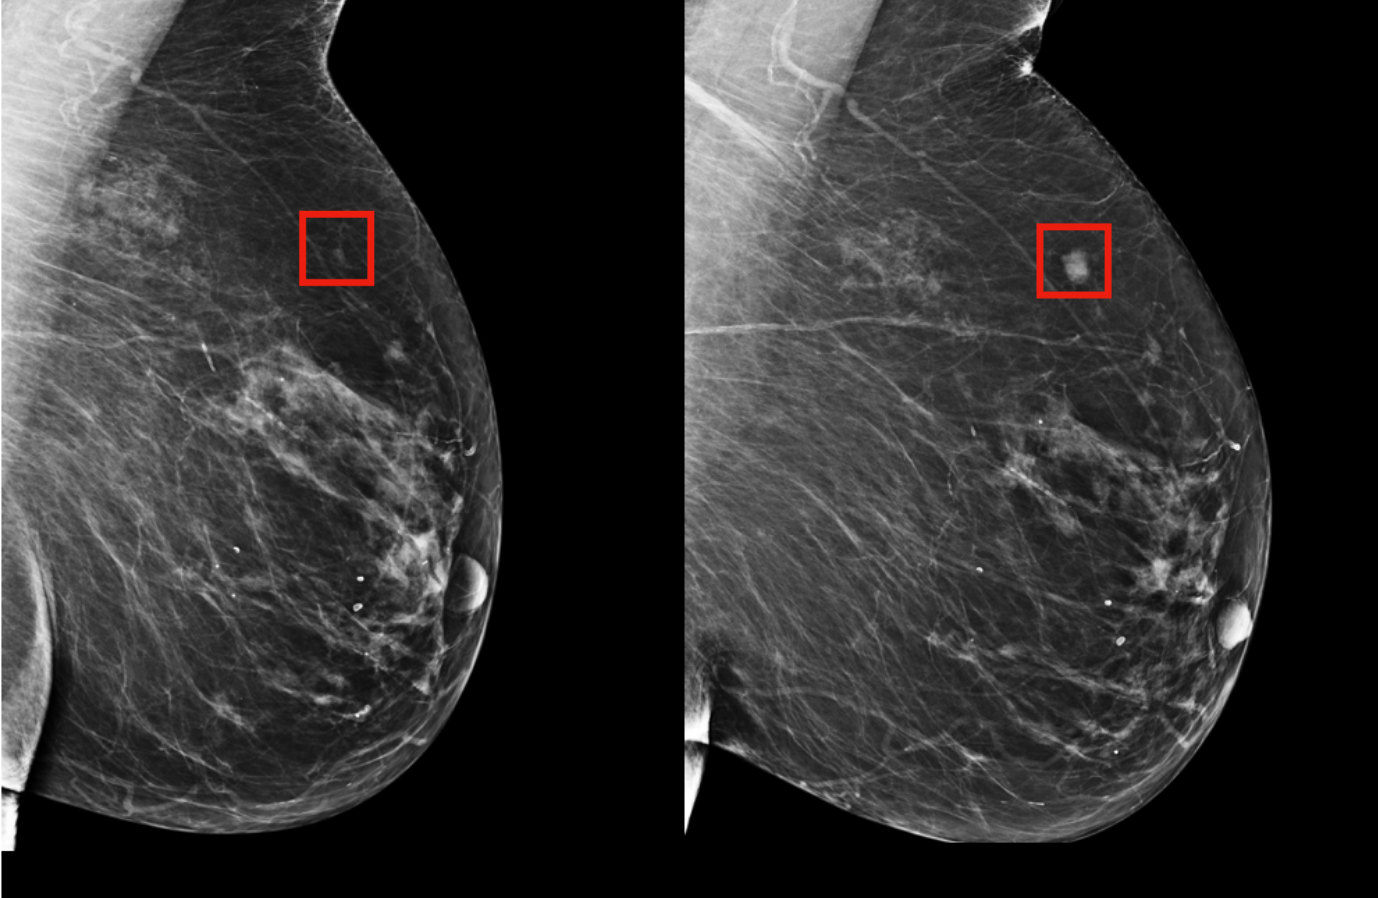

Breast Cancer Detection

Our deep learning model analyzes mammograms and ultrasound images to detect breast cancer, improving early diagnosis rates.

Breast Cancer Mammogram